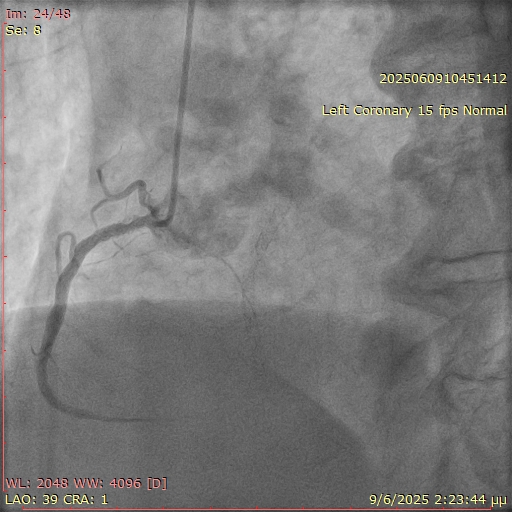

A 67-year-old man with a history of coronary artery disease and prior percutaneous coronary interventions (PCI) of the left anterior descending artery and the right coronary artery (RCA) presented with stable angina. During diagnostic coronary angiography, selective engagement of the RCA using a 5F Judkins right (JR) 4 catheter proved challenging (Figure 1). However, angiographic signs suggested significant restenosis at the ostium and proximal RCA. PCI was initiated using a 6F JR 4 guiding catheter; operators employed the "floating wire" technique, maintaining the wire at the catheter tip until ostial engagement was achieved. After several attempts, the wire was successfully advanced distally into the RCA.